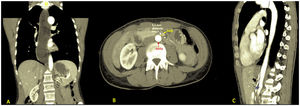

We present the case of a 46-year-old woman diagnosed with megaoesophagus, with previous normal functional tests. Computed tomography showed megaoesophagus (Fig. 1A) secondary to a change in calibre in the third duodenal portion with an aortomesenteric distance of 6.2 mm (Fig. 1B) and an angle of 25° (Fig. 1C), characteristic of Wilkie’s syndrome. Her symptoms resolved after a duodenojejunostomy was performed, with adequate oral tolerance. Wilkie’s syndrome is an unusual cause, but should be included in the differential diagnosis of megaoesophagus.